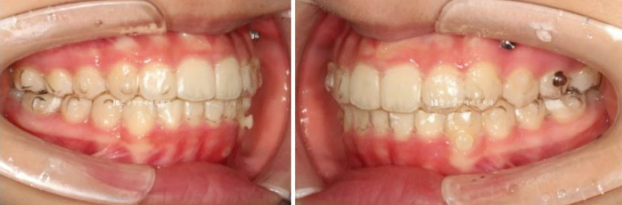

23.08~24.07

무엇보다 한쪽의 3급 어금니 교합관계는 1급이 되었습니다.

치료가 잘 끝났으니 1년간의 변화를 보겠습니다.